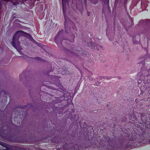

Histopathologic examination reveals a relatively well-circumscribed lesion in the upper two-thirds of the dermis with a focal epidermal connection. It is composed of basaloid aggregations arranged predominantly in columns and cords and admixed with infundibulocystic structures, surrounded by a dense, hypocellular desmoplastic stroma. It may occasionally be difficult to distinguish this entity histologically from malignant desmoplastic lesions such as aggressive growth basal cell carcinoma or MAC. Treatment. Local surgical excision is the preferred treatment